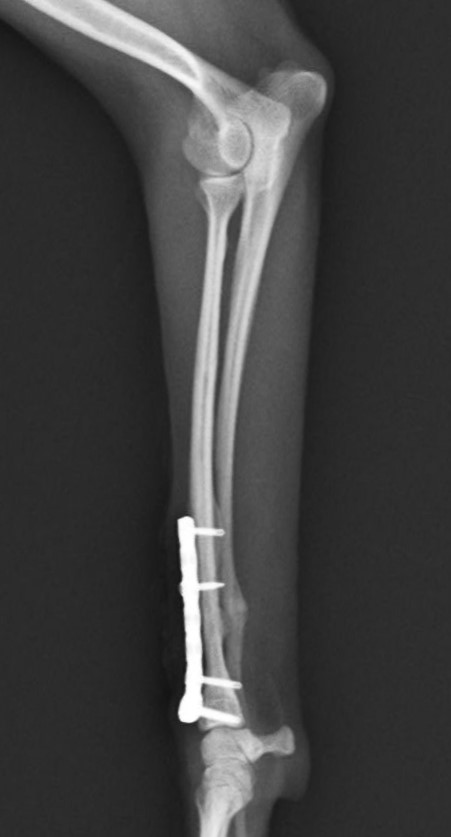

左前腕骨折のトイプードルちゃんの手術がありました。橈尺骨骨折は動物病院では一番よくある骨折です。ロッキングプレートであるTAITANコンディラー1.7mmで対応しました。治りも順調で元気に帰りました。よかったね。